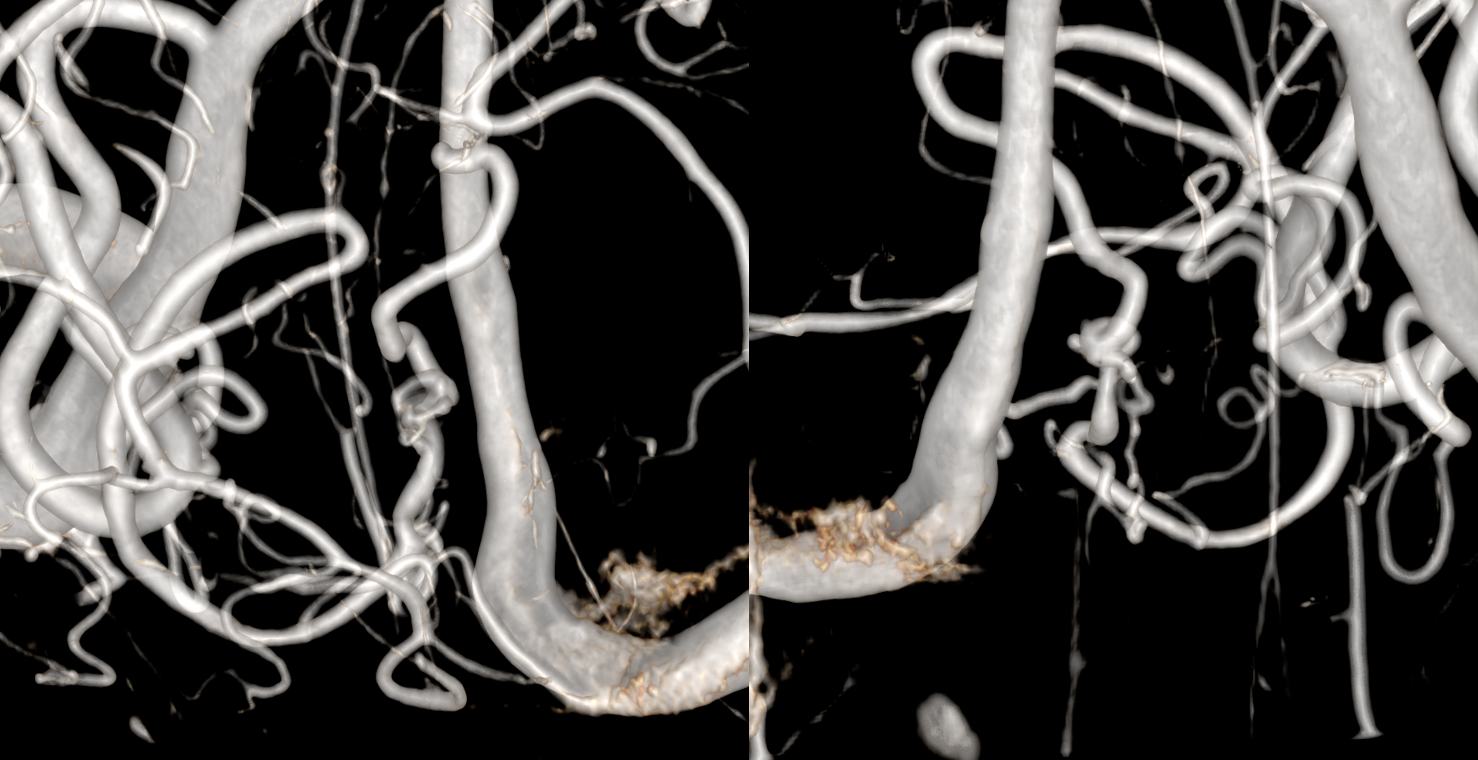

Not much to be seen in the standard DYNA — even the region of interest is not there

More suspected from a dedicated view of the standard recon

With more image manipulation, diagnosis is certain. That two channels reconstitute the distal PICA — strongly suggesting that the dissection has been around for some time, and hemorrhage likely comes from the hypertrophied new channels reconstituting the distal PICA — they used to be microscopic and are do not do well being many more times their intended size. This is a similar process to what is seen with hemorrhagic Moya Moya